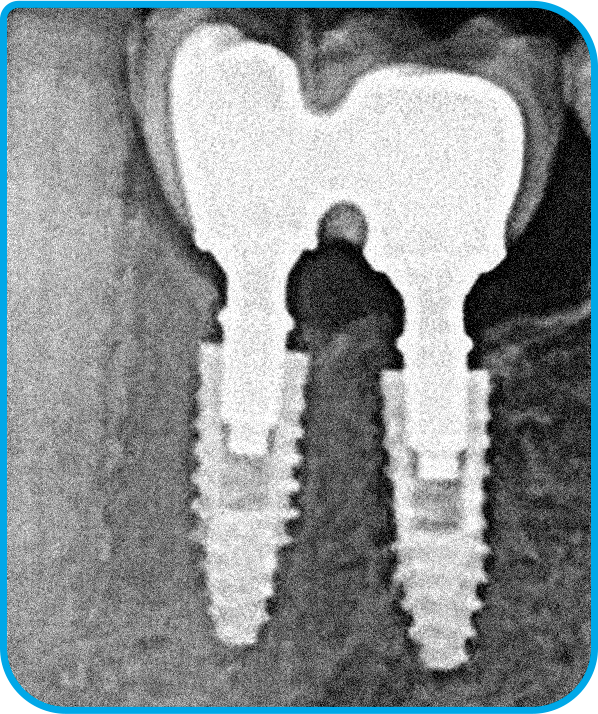

O caso clínico iniciou-se em 2015 com o objetivo de restaurar função e estética. Foram instalados dois implantes nas regiões dos dentes 35 e 36, seguidos pela osseointegração e condicionamento tecidual. As próteses finais foram confeccionadas sobre pilares Arcsys, com ajustes oclusais precisos. O acompanhamento clínico completa dez anos, com exames periódicos e manutenção regular. Observa-se excelente estabilidade óssea e saúde peri-implantar. O caso comprova que protocolos bem executados e componentes de qualidade garantem longevidade previsível.

2 | Imagem radiográfica após a instalação dos implantes e componentes protéticos.

3 | Exame de imagem realizado 120 dias de pós-operatório, após instalação da prótese.

4 | Acompanhamento radiográfico de dois anos em função.

5 | Imagem radiográfica evidenciando a estabilidade tecidual ao redor dos implantes após dez anos de função.